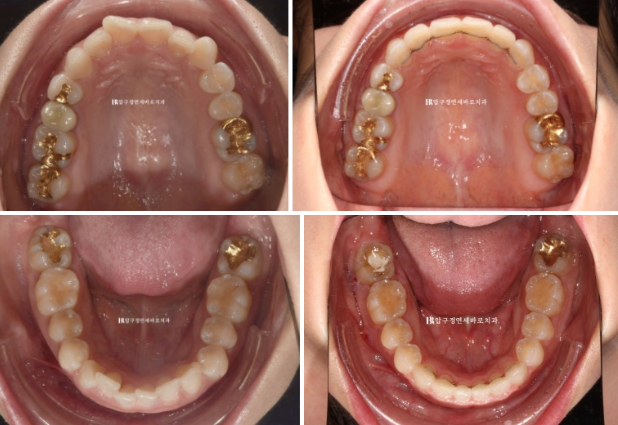

23.04~24.10

잇몸 노출량이 줄면서 잇몸미소 거미스마일 많이 좋아졌죠?

소량의 입동굴이 생겼고 과하지 않은 입동굴은 여성스러운 미소 심미를 개선시킵니다.

돌출되지도 옥니처럼 쓰러지지도 않는 일자로 딱 떨어지는 적절한 앞니 각도 개선된 잇몸 노출량

비포 애프터 사진을 보면 환자분들은 그제서야 내가 잇몸이 원래 많이 보였구나 하고 감탄하십니다.

입술 위치는 1~2mm 정도 뒤로 들어갔습니다.

치아 뿌리 평행도도 좋고 치근흡수 등 부작용은 관찰되지 않습니다.